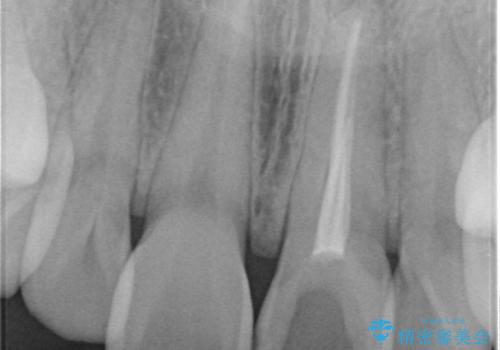

- 前歯の変色を主訴に来院された患者様です。

より審美的な修復を行いたいとのことであったため、ジルコニアクラウンでの修復を行います。